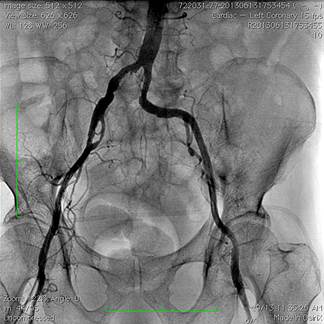

Hình 2: Van động mạch chủ CoreValve được đặt đúng vị trí

Dây dẫn Amplatz siêu cứng kích cỡ 0,035 inch (hãng Boston Scientific, Hoa Kỳ) được đẩy xuống buồng thất trái qua sheath 18 French. Tiến hành nong van động mạch chủ sử dụng bóng đường kính 22 mm, chiều dài 30 mm (hãng NuMED, Hoa Kỳ) khi tiến hành tạo nhịp thất nhanh. Sau đó, van sinh học CoreValve kích thước 29 mm được đặt ở vòng van động mạch chủ dưới hướng dẫn của màn huỳnh quang tăng sáng. Bệnh nhân xuất hiện bloc nhĩ thất độ 3 thoáng qua sau khi đặt van, tuy nhiên sau đó tự hồi phục về nhịp xoang. Kết quả chụp động mạch chủ cho thấy van động mạch chủ nhân tạo nằm đúng vị trí, chỉ có hở rất nhẹ cạnh chân van. Thông tim cho thấy không còn chênh áp qua van động mạch chủ (hình 3). Siêu âm tim qua thực quản và chụp gốc động mạch chủ ngay sau khi đặt van cho thấy van nằm đúng vị trí, hở rất nhẹ quanh van (hở độ I). Sau khi đã kiểm tra vị trí van trên phim chụp mạch cản quang và siêu âm tim, sheath 18 Fr được rút ra và động mạch đùi được đóng lại bằng 2 dụng cụ Perclose.